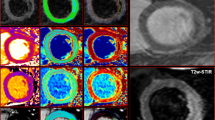

Otsu’s Automated Thresholding (OAT) method. Top row: Short-axis late gadolinium images from basal to apical (left to right). Middle row: Enhancement (yellow) signifying infarct, designated on a slice-by-slice basis by OAT method. Bottom row: OAT automatically identifies hyperenhanced areas by selecting the grayscale signal intensity threshold (red) on a slice-by-slice basis that gives the minimal intraclass variance within enhanced and normal myocardium.

AAR quantification

AAR was quantified on T2w-STIR as hyperenhancement using 2SD thresholding and OAT by 2 blinded readers (JNK, SAN). The ROI size for 2SD was set at 2 cm2. Mean AAR was compared across the techniques and with manual quantification as described above for IS quantification.

Infarct size and Area-At-Risk quantification at 3.0T. Top/middle rows: IS on a single patient at 3.0T demonstrating increasing IS using FWHM, 5SD and OAT, and decreasing IS from 5–8 SD. FWHM and 8SD closely correlated with the reference standard of manual quantification. Bottom row: AAR in the same patient using OAT and 2SD thresholding was non-significantly greater than the reference standard of manual quantification. FWHM = full-width half maximum, 2/5/6/7/8SD = >2/5/6/7/8 standard deviations, OAT = Otsu’s Automated Thresholding.

AAR extent

AAR varied with the quantification method used (Figures 4 and 5). There was no significant difference between 2SD, OAT and manually quantified AAR at 1.5T. At 3.0T, AAR quantified with OAT was larger than that manually contoured (p = 0.004) and similar to that on 2SD. Agreement with manual quantification at 1.5T tended to be higher for OAT than 2SD, with ICC 0.920 and narrower limits of agreement on Bland-Altman analysis. There was no difference in AAR quantification time using OAT, 2SD or manual quantification at 1.5T or 3.0T (Table 5), Additional files 4 and 5.